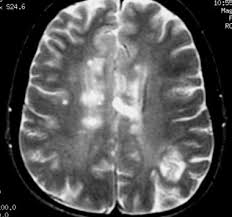

APP demo - https://www.youtube.com/watch?v=xbZUBd_1fSQ Presentation - https://www.youtube.com/watch?v=trTC5IrCSWA A doctor/ patient can make an account on our web app and then he can go to the "scans" page and upload an x-ray/ MRI of a specific organ. Our AI algorithms will detect if a disease is present in that scan.

This is a dynamic web app that uses artificial intelligence so this makes it a very complex the app when it comes to the backend part. We used the python programming language as it is very easy to program with it and is probably the best programming language for data science. Python also has some very good web engines. We used the Jinja template engine used by Flask in python. Flask is a very good choice in this case as it is highly customizable has many useful libraries and is very well documented. For the forms, we used - Flask-WTF For the login dynamic - Flask-login For the database, we use a Postgres link connection with Flask-SQLaclhemy We also need a background worker for Artificial Intelligence algorithms as they take a long time and making the user wait is not an option in this case, especially if they have a slow internet connection. As a python client, we used Redis and RQ workers to send background jobs in the queue. For the artificial intelligence algorithms, we used, ( along with popular linear algebra libraries like NumPy ), the TensorFlow library which is the most popular neural network library and it provides powerful algorithms like ResNet50, which we used to train the Brain Tumor and Pneumonia algorithms. The datasets come from Kaggle. Brain tumor dataset: https://www.kaggle.com/navoneel/brain-mri-images-for-brain-tumor-detection Pneumonia dataset: https://www.kaggle.com/c/rsna-pneumonia-detection-challenge We had to show the results in a web page and we did that by making a waiting web page that refreshes every 10 seconds and therefore sends a request every 10 seconds, in that request, we also check if the background job is ready. If it is ready to take the output, ( the image ha to be converted to bytes encoded in utf-8 as this is the safe and sure way of transferring images through workers). We hosted our app with Heroku ( paid for hobby plan so the app won’t sleep) as it is very easy to use workers, postgress, make multiple uploads, etc.